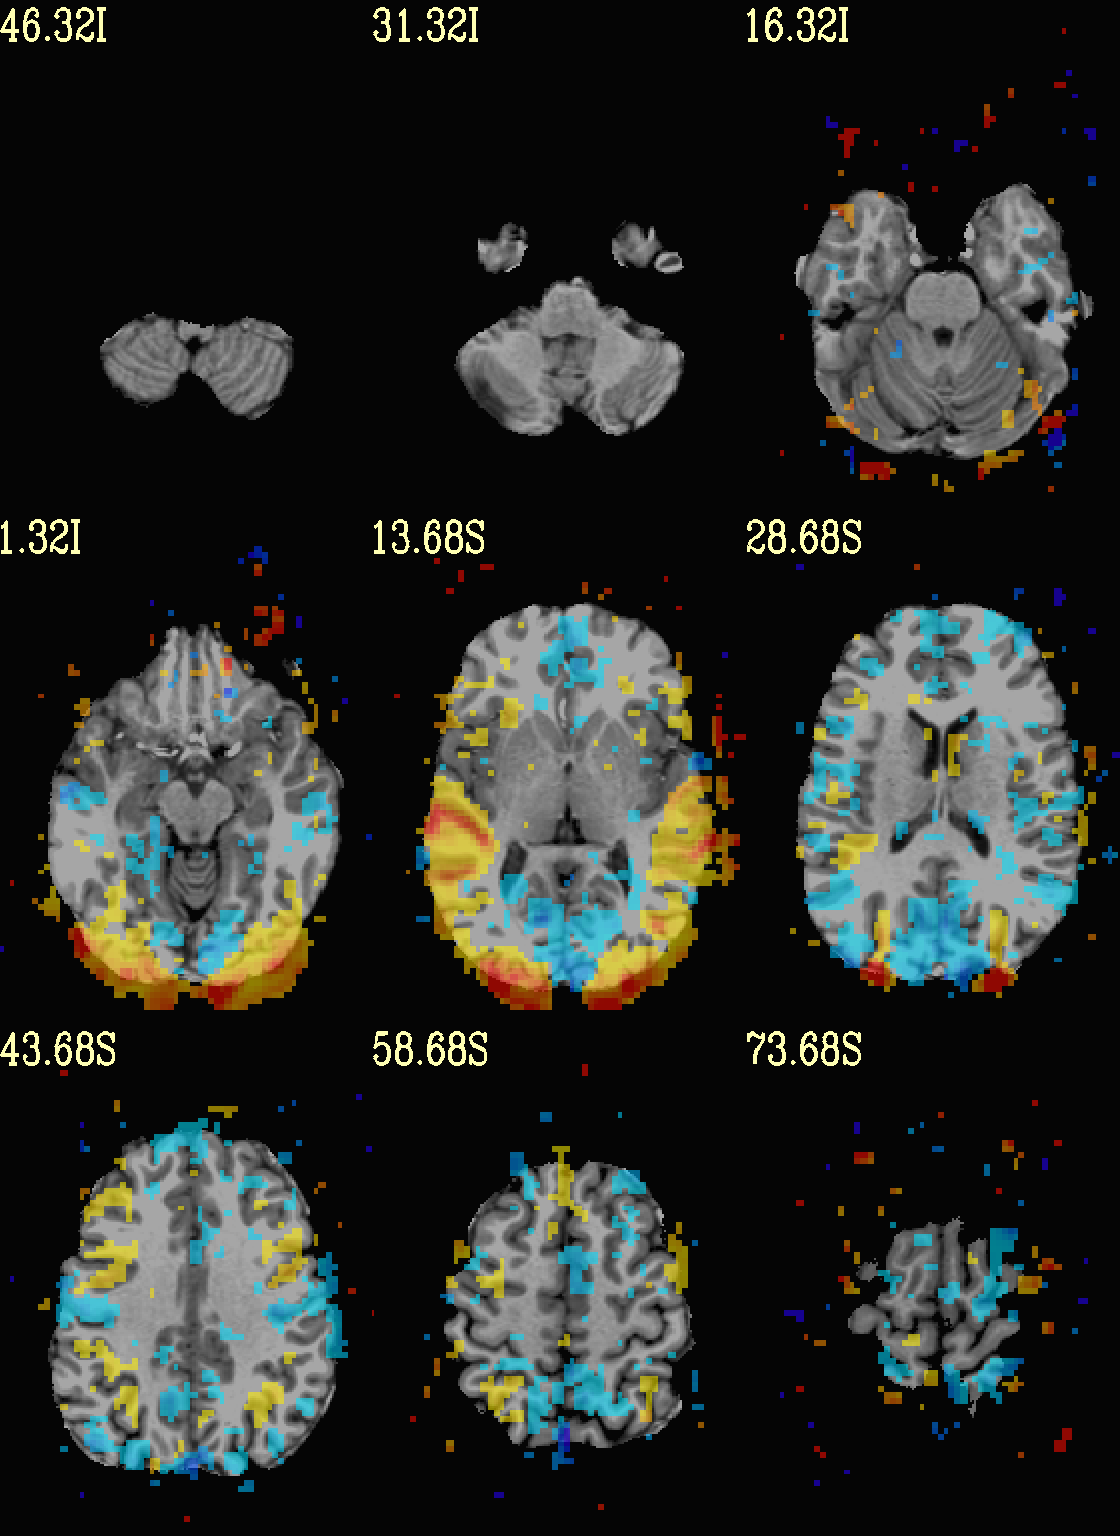

Ex. 7: Overlay beta coefs, threshold+clusterize translucently¶

Following on from the previous couple of examples, we can actually apply thresholding (by statistics) and clusterizing with translucent thresholding, using the alpha+boxed methodology from above. This can be a very useful way to highlight some results, while showing more results of modeling.

Therefore:

voxels that are both above voxelwise threshold and in a suprathreshold cluster will be opaque (or at max opacity) and boxed;

voxels that are above voxelwise threshold but not in a large enough cluster will be just slightly translucent and not boxed;

voxels that are below voxelwise threshold (and couldn’t even be in a cluster) will have the usual transparency increasing with their decreasing values.

So, there is a lot happening here. The “trick” with getting this

functionality to work properly is knowing what parameters need to go

where. Which is why we have examples like this! But you might also

want to check out the @chauffeur_afni help.

See how we use -set_subbricks .., -clusterize ..,

-thr_olay_p2stat .. and -thr_olay_pside .. here (and notice

our input for -olay .. is the coefficient+stats dset again, like

we put into 3dClusterize above):

NB: the cluster report text file is also output,

${opref}_clust_rep.txt.

set opref = QC/ca007a_Vrel

@chauffeur_afni \

-ulay strip+orig.HEAD \

-box_focus_slices AMASK_FOCUS_ULAY \

-olay func_slim+orig.HEAD \

-cbar Reds_and_Blues_Inv \

-ulay_range 0% 130% \

-func_range 3 \

-set_subbricks -1 "Vrel#0_Coef" "Vrel#0_Tstat" \

-clusterize "-NN 1 -clust_nvox 200" \

-thr_olay_p2stat 0.001 \

-thr_olay_pside bisided \

-olay_alpha Yes \

-olay_boxed Yes \

-opacity 5 \

-prefix ${opref} \

-set_xhairs OFF \

-montx 3 -monty 3 \

-label_mode 1 -label_size 4

Example 7a |

As noted just above, one typically uses a mask when clusterizing (because the cluster size threshold would likely have come from looking at the spatial smoothness of noise just within the brain, not within the entire FOV). That mask can also be included in the commands clusterizing; conveniently, the final images will still show data from the entire FOV, and the boxed voxels will only be within the mask.

The only change from the previous command here is including a -mask

.. option in the chauffeur’s -clusterize .. option, as follows.

Note how the larger clusters that stuck outside the brainmask above

now show the mask’s boundary line—this is particularly apparent in

the posterior part of the brain/FOV.

set opref = QC/ca007b_Vrel_mskd

-clusterize "-NN 1 -clust_nvox 200 -mask mask.auto.nii.gz" \

Example 7b |